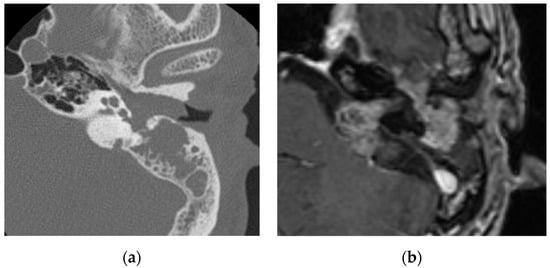

2.6. Middle Ear and Mastoid